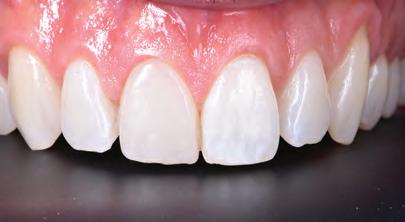

FIGURE 2: Initial treatment focussed on patient-driven improvements in oral hygiene, supplemented by professional mechanical plaque removal and ongoing fourmonthly supportive periodontal therapy. The patient demonstrated a sustained commitment to oral health behaviour change, as evidenced by the establishment of a robust, pale, pink and stable gingival architecture.

At the laboratory, the dental technician may merge these digitised records using Zirkonzahn.Modifier software (Zirkonzahn Srl; Gais, Italy) to form a precise 3D rendering of the patient’s pre-operative dentofacial situation, with all biomechanical and aesthetic landmarks conveniently available for reference. This offers the technician unparalleled, high-fidelity access to key diagnostic clinical information when compared to conventional analogue-based workflows.4 At this stage, an end goal of prosthodontic treatment may be developed wherein the contours of the proposed restorations are informed on the basis of the patient’s physiognomy, or rather, their unique and characteristic facial features (Figure 4).9 The final proposed design may be fabricated into a snap-on smile try-in, or treatment mock-up, using a flexible machinable polycarbonate (Temp Premium Flexible; Zirkonzahn Srl, Gais, Italy) (Figure 5).

At this early stage of diagnostic work-up, prior to any operative intervention, the clinician and the technician can now communicate to each other and, most importantly, to the patient, in an understandable visual rhetoric, a precise end goal of treatment from which a meeting of the minds may be achieved (Figures 6 and 7).5

Given the serious, irreversible and biologically expensive nature of prosthodontic treatment modalities, a precise end outcome of treatment should be visualised in a language that all stakeholders can understand prior to undertaking significant changes to a dentition. Complete digital workflows that allow the combination of dentofacial 3D data are emerging as an indispensable contemporary tool for restorative clinicians.16